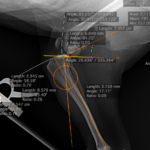

CBLO #205 超小型犬の前十字靭帯断裂に2.0 CBLOで対応しました。しばらく安静が必要です。 症例カテゴリー 放射線治療整形外科軟部組織外科脳神経外科内科腫瘍外科救急・集中治療リハビリテーション科腫瘍内科内視鏡科脳神経科呼吸器外科中医・漢方猫の腎移植循環器科